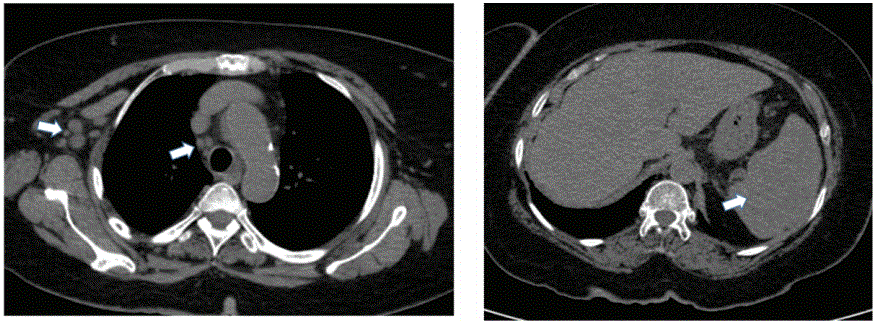

图1:高分辨率胸部CT示右上肺叶钙化结节(白色箭头),淋巴管周围和小叶中央分布有大量小结节(黑色箭头),与随机分布的间质结节一致。

一位62岁的沙特女性到急诊科(ED)主诉有两个月的食欲减退史,体重下降约10公斤,周期性的主观发热。同时,她也有呼吸急促和咳白痰的病史。她不吸烟,也不知道以前没有诊断过肺结核,也没有接触过确诊的肺结核病例。用药史显示她目前服用艾司西酞普兰治疗抑郁症,有阿达木单抗治疗银屑病史;她的最后一剂药是九个月前她已经服了一年了。患者否认使用过任何皮质类固醇,也不知道她以前是否做过肺结核筛查。她住在南部(国际足联在沙特阿拉伯的吉赞旁边)。她养了很多猫;没有接触过鸟类、鸽子窝或鸡舍;附近没有建筑或拆除,她也从未出过国。 Physical examination: revealed a pale-looking elderly cachectic with Parkinson’s disease feature. Chest examination showed bilateral upper lobe crackles with decreased air entry on the right side. Initial laboratory works showed a normal range of white blood cell count (WBC), no anemia with normal hemoglobin value, normal renal functions with normal value of blood urea nitrogen (BUN), and creatinine. Normal value of albumin-Human immunodeficiency virus (HIV) Ag/Ab combo nonreactive HBsAg nonreactive, hepatitis C virus Ab Nonreactive, C-reactive protein (CRP)12, antinuclear antibodies (ANA) at<1:80, hypercalcemia with calcium level at 2.60 mmol/l (2.12-2.252). Radiologically, Chest X-rays showed a moderate amount of pleural effusion in the right lung with right lower lobe consolidations and nodular opacities in the right middle zone. Hence, a chest computed tomography (CT) scan showed bilateral pleural effusions with associated bilateral basal pulmonary nodules and background of interstitial lung disease and bilateral bronchiectasis changes affecting the posterior segment of its lower lobes as well as in the right middle lung lobe. Furthermore, the abdomen CT scan shows omental thickening anterior to the transverse colon and multiple splenic focal lesions and few para-aortic subcentimetric lymph nodes as per figures 1-4.

图2:纵隔窗显示轻度纵隔和右侧腋窝淋巴结病变。也有轻微的脾肿大。

图3:CT示进行性肺结节增大,少数开始形成中心空泡。

图4:纵隔窗显示右侧腋窝大淋巴结间期钙化,脾脏可见大量钙化灶。